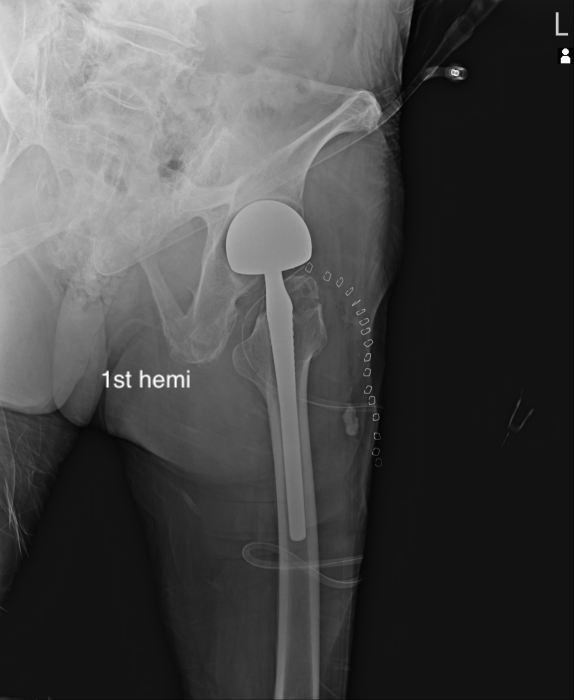

대퇴관절에서 대퇴골 경부가 골절이 있는 경우 시행하는 치료는

Osteosynthesis, 혹은 BPA, 혹은 THA 로 나뉠 수 있습니다. 최근 THA는 Dual Mobility Articulation 등을 사용해서 ROM 을 증가시키고 Dislocation 을 감소시키고 있긴 합니다.

THA 는 비구면 까지 고정을 하기 때문에 거의 마지막 수술이자 완벽한 수술이라고 볼 수 있습니다. 하지만 비골두가 안정적인 경우에는 골두치환만 해도 충분히 '인공관절' 기능을 할 수 있으며 수술적 시간이 매우 적습니다. 물론, 비골두가 implant 에 맞는 알맞은 구형 형태와 크기를 갖고 있어야 합니다. (36mm 를 많이 사용합니다. )

BPA 는 대퇴골두를 제거하고 인공 대퇴골두를 넣게 되는데, 인공 대퇴 골두와 이것을 감싸는 라이너가 있어 이 두개 사이의 움직임이 존재하며, 라이너와 골반 사이의 움직임이 존재하여 양극성(Bipolar) 인공관절 반치환술 이라고 불립니다.